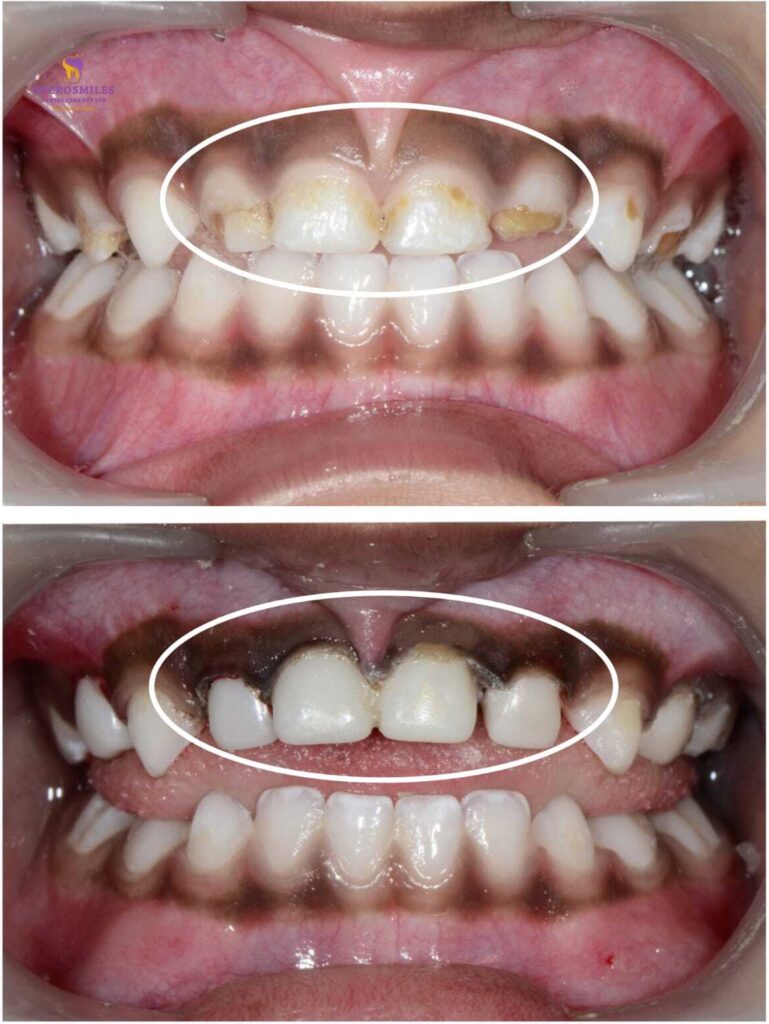

When your child’s tooth needs more than a filling, you want a solution that’s strong, safe, and looks just like a natural tooth. At Microsmiles Dental Care, our Zirconia Crowns / Ceramic Caps are the ideal choice for restoring damaged or decayed baby teeth-without compromising on appearance or comfort.

These aesthetic, child-friendly crowns offer long-term protection with a natural look that keeps your child’s smile bright and confident.

While stainless steel crowns are functional, they often leave a metallic look. Zirconia crowns, on the other hand, offer the strength of metal with the beauty of ceramic, making them the preferred choice for visible front teeth or parents seeking a more natural aesthetic.

Unlike traditional options, these crowns help children smile, speak, and eat confidently-without anyone noticing they’ve had dental treatment.